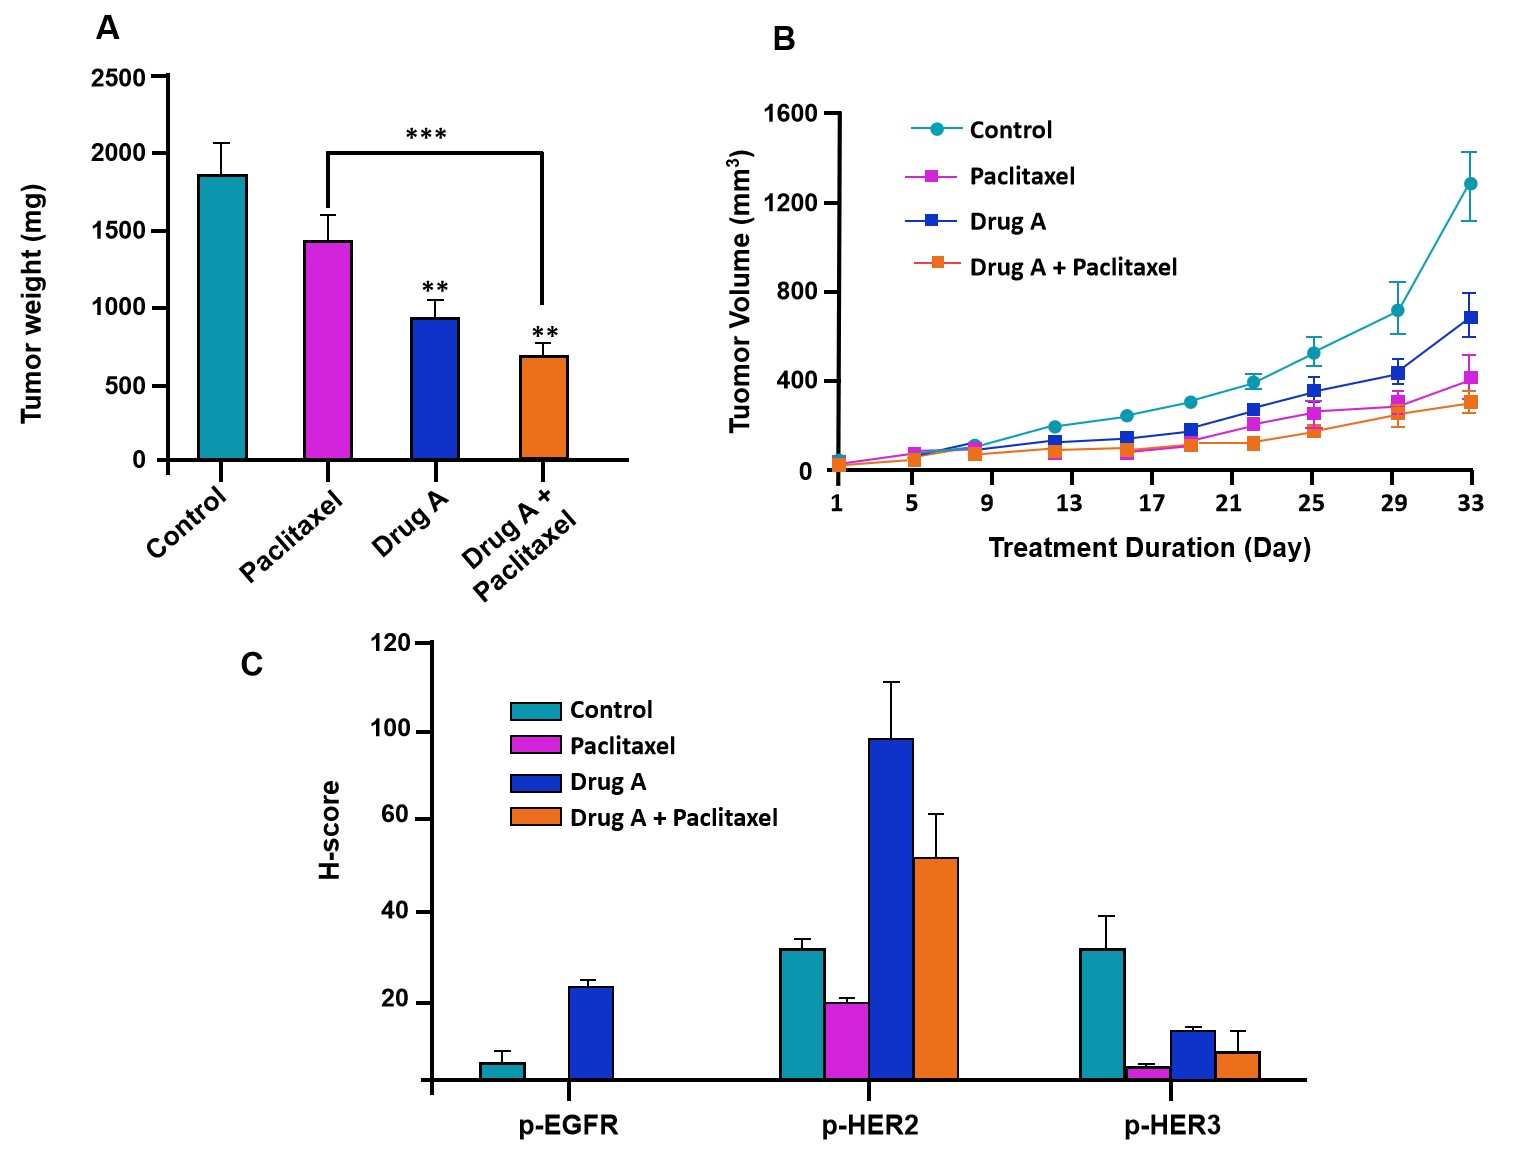

This case utilized the established SUM149 CDX model to systematically evaluate the anti-tumor efficacy of the investigational drug A, both as a single agent and in combination with the chemotherapeutic drug paclitaxel.

- Effective Tumor Growth Inhibition: In the SUM149 CDX model, drug A monotherapy demonstrated significant anti-tumor activity. However, the combination of drug A with paclitaxel was substantially more effective, resulting in superior tumor growth suppression compared to either single agent alone (Fig. 2A, B).

- Mechanism validation (Ex Vivo): Immunohistochemical analysis confirmed the target mechanism of action of this compound, namely, significant inhibition of phosphorylation of EGFR, HER2, and HER3 in resected tumors (Fig. 2C).

Fig. 2 Efficacy evaluation of drug A. (A)*p < 0.01 (vs. control), **p = 0.01 (vs. paclitaxel + Drug A); (B) *p < 0.05 (vs. control); **p < 0.01 compared to control.) (Source: Alfa Cytology)

Fig. 2 Efficacy evaluation of drug A. (A)*p < 0.01 (vs. control), **p = 0.01 (vs. paclitaxel + Drug A); (B) *p < 0.05 (vs. control); **p < 0.01 compared to control.) (Source: Alfa Cytology)